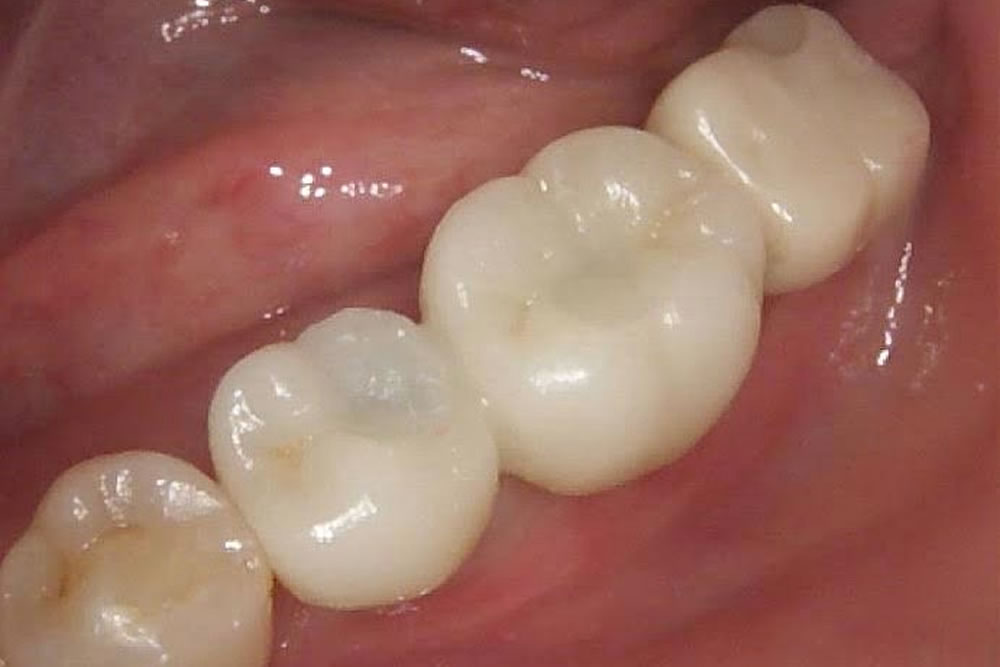

骨ができるまでには6ヵ月と少し通常よりも時間がかかりましたが、しっかりと上部の歯まで作成していきました。

結果、通常通りに食事をする事ができるようになったと満足して頂く事ができました。